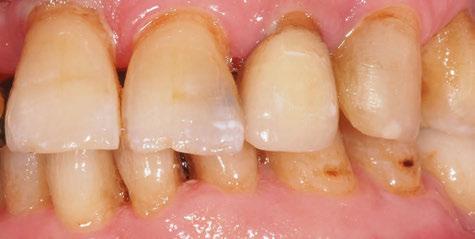

A partir del estudio radiológico y de las imágenes fotográficas podemos observar edentulismo de 17, 15, 14, 12,

Figura 1a. Foto intraoral frontal inicial.

Figura 1b. Foto intraoral lateral izquierda inicial.

Figura 1c. Foto intraoral lateral derecha inicial.

25, 26, 28, 37, 38, 47 y 48. Presentaba corona desajustada en 13 con extensión en 12, implantes en 35-36, 45-46, con coronas ferulizadas en 35-36, 45-46, y dientes anteriores superiores con enfermedad periodontal Grado IV.

2. Exploración de tejidos blandos

El paciente presentaba biotipo periodontal grueso, con márgenes asimétricos, con recesiones gingivales a nivel de 11 y 13 y pérdida de tejidos blandos interproximales.